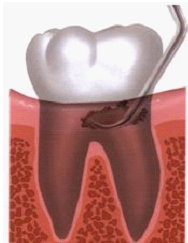

所有治療前都必須透過 牙周囊袋測量,

來判別牙周受破壞的程度、以及需要何種治療,

醫師會先拿一根 牙周探測器,插入牙齦溝測量深度,

健康時,牙齦溝的深度大約1~3釐米,

大於3釐米就表示已形成囊袋,越深代表牙周破壞越嚴重。

簡單介紹一下:

▷早期輕度牙周病通常可經由正確刷牙及用牙線潔牙而恢復健康。

▷當 牙菌斑堆積 並硬化成牙垢時,

牙醫師提供的專業處理,就是清除牙結石。

牙醫師會 清潔或「刮除」牙齒與牙齦線上下方的牙結石,

此為「牙根刮除術」。

若情況較為嚴重,可能會進行「牙根整平術」,

牙根整平術可使牙齒根部的不規則處變平滑,讓牙菌斑更難沈積。

至於位在深層,牙根周圍、齒槽骨遭破壞的程度,

就需用全口X光檢查透視。

如果牙齒開始動搖,就要檢查牙齒動搖度。

光用手指觸碰無法得到正確讀數,要利用兩支鈍端的器械,

通常是口鏡及牙周探測器的柄,才能測得牙齒鬆動的程度。